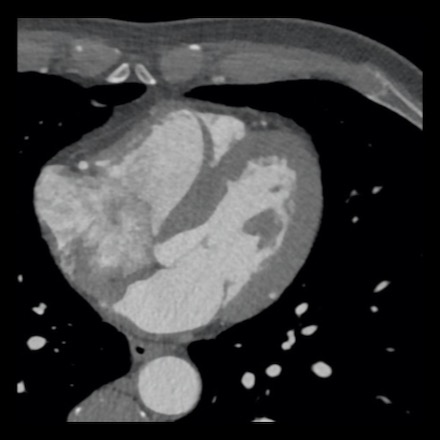

case 4 – CAD-RADS 3/P1/I+ thrombus left ventricle

First, scroll through the CTA images.

How would you describe the findings on the coronary CTA?

The findings are:

- Moderate (50-69%)

stenosis in the proximal LAD caused by a non-calcified plaque. - Variant of

sinoatrial (SA) nodal artery. The artery usually arises from the RCA as a second

branch after the conus artery, however in this case it arises from the LCX,

courses behind the aorta, anastomosing with the right atrium and with a small

branch supplies the SA-node of the heart. - Thrombus in the

apex of the left ventricle. - CTP was performed

in this patient. CTP showed a perfusion defect at stress imaging in the

territory of the LAD (I+), at rest no perfusion defect was visible.

This patient classifies as CAD-RADS 3/P1/I+, which means

this patient requires further investigation.